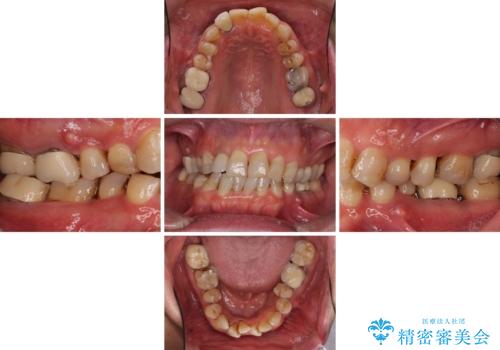

- 前歯のデコボコや、奥歯を咬んだときに痛みがあるとのことで来院された患者様です。

全体的に問題が多く、全てをしっかりと治療したいとのことでした。

全体的に中等度の歯周病と診断されたため、歯周外科処置やインプラントによる咬合回復から進めて行き、矯正治療による歯列改善を行った後にオールセラミッククラウンにて補綴することとしました。